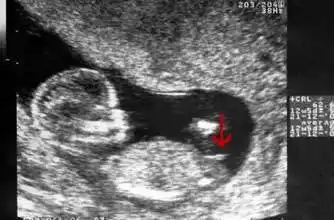

那个"小块块"是宝宝发育时期出现的一个部位,每个宝宝无论男女都会有